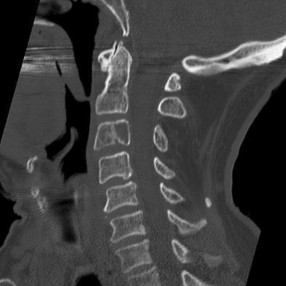

A 78-year-old male presents after a fall from standing. CT of the cervical spine demonstrates a displaced Type II odontoid fracture. Which of the following factors has been shown in the literature to be the strongest predictor of nonunion if this patient is treated non-operatively in a cervical collar?

Explanation

Type II odontoid fractures have a high rate of nonunion, particularly in the elderly. Risk factors for nonunion include patient age >50 years, initial fracture displacement >5 mm, posterior displacement of the dens, and initial angulation >10 degrees. While halo vests provide stiffer immobilization than collars, they carry significant morbidity in the elderly. The degree of initial displacement (>5 mm) remains one of the most critical intrinsic fracture characteristics predicting failure of non-operative management.